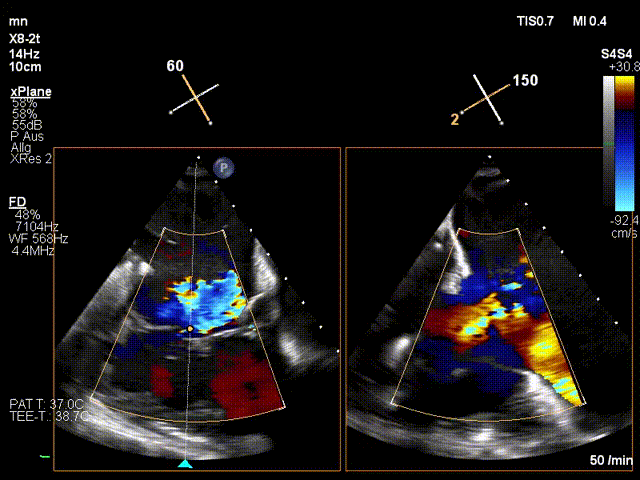

手術(shù)在全麻狀態(tài)下進(jìn)行。在加拿大圣保羅醫(yī)院的Anson Cheung教授的指導(dǎo)參與下,術(shù)者采用經(jīng)右側(cè)頸靜脈入路的方式將輸送器送入患者心臟內(nèi),在TEE及DSA引導(dǎo)下調(diào)整輸送器頭端角度,使得輸送器與三尖瓣瓣環(huán)平面垂直。在輸送器進(jìn)入右心室后釋放室間隔錨定裝置,而后釋放瓣葉夾持件(2個耳片結(jié)構(gòu))成垂直狀態(tài)。在TEE及DSA確定夾持件固定至三尖瓣葉根部且位于右室側(cè)后釋放人工瓣心房側(cè)盤片。隨后調(diào)整瓣膜同軸性以及室間隔錨定件位置(貼合室間隔),前推藏針管并固定,進(jìn)而釋放室間隔錨定裝置,并再次確認(rèn)瓣膜位置、穩(wěn)定性及同軸性,合攏輸送鞘后撤出輸送器,完成LuX-Valve Plus人工三尖瓣瓣膜的植入。

LuX-Valve Plus經(jīng)血管三尖瓣置換系統(tǒng)本次“出海”圓滿完成,術(shù)后Jörg Hausleiter教授對LuX-Valve Plus經(jīng)血管三尖瓣置換系統(tǒng)的器械性能和治療效果大為稱贊,認(rèn)為LuX-Valve Plus的手術(shù)體驗(yàn)非常好。術(shù)后即刻超聲顯示三尖瓣反流消失,血流動力學(xué)改善顯著,患者恢復(fù)快。Anson Cheung教授也肯定了LuX-Valve Plus術(shù)中操作的便捷性,認(rèn)為LuX-Valve Plus容錯率高,對術(shù)中影像的依賴較小,后期希望可以更多的應(yīng)用LuX-Valve Plus三尖瓣置換系統(tǒng)于臨床實(shí)踐,讓更多的三尖瓣重度反流患者盡早獲益,改善預(yù)后。